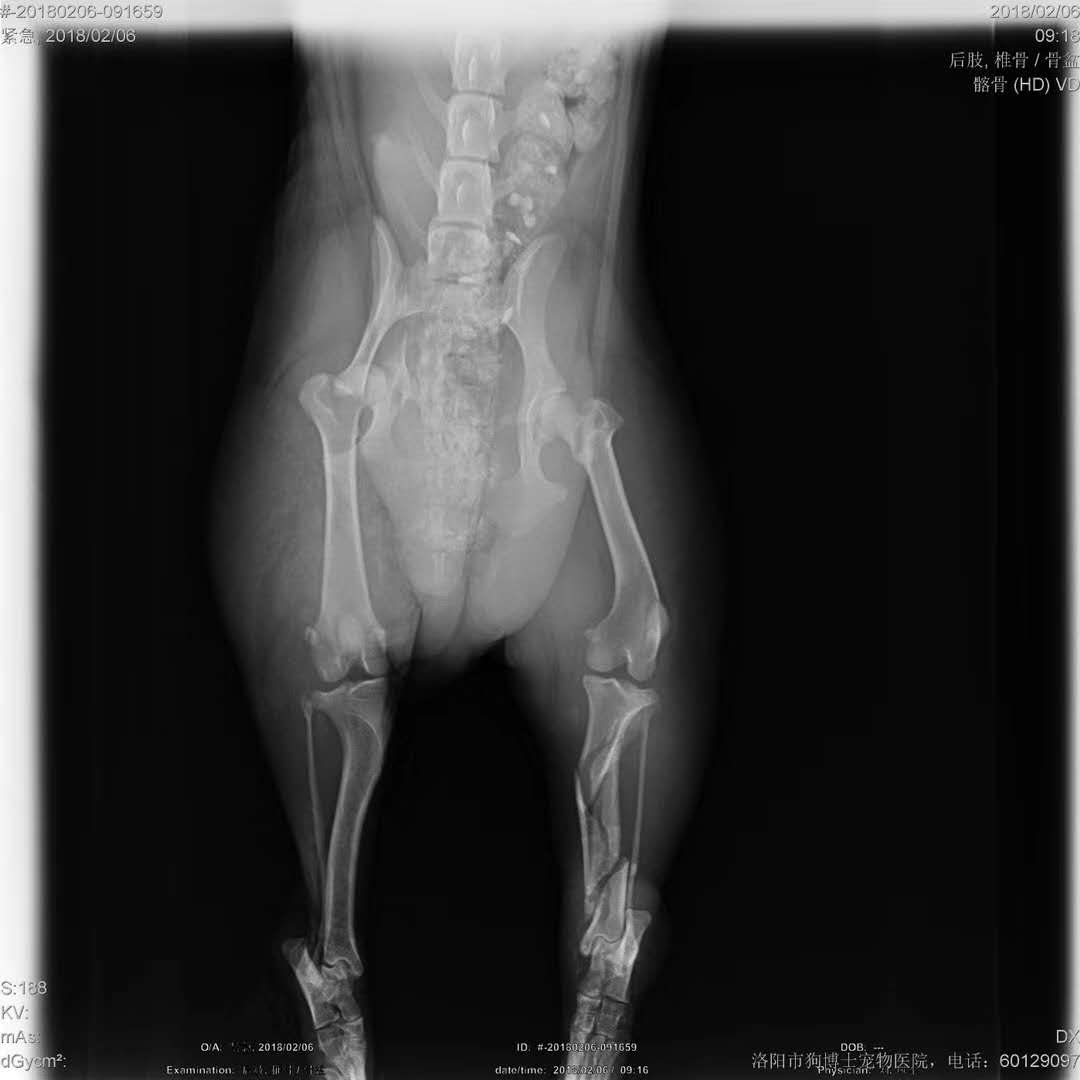

救助粉碎性骨折狗狗籌善款:好心人 常先生 于今早在王城大道與中州路口附近,救助一條黑色泰迪,昨后腿疑似被外力擊打致粉碎性骨折,送至我院進(jìn)行治療,因病情較重,治療費(fèi)用較高,現(xiàn)向社會籌集救助善款,捐款者可以直接發(fā)到劉鳳軍院長微信上(13698844707),您的善舉可以還狗狗一個健全的身體,感謝大家捐款或者轉(zhuǎn)發(fā)。